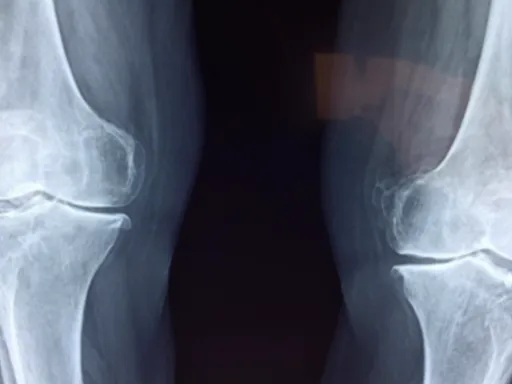

퇴행성 관절염

나이가 들면서 관절 연골이 닳아 염증이 생기는 질환이에요. 오른쪽 골반 관절에 퇴행성 변화가 오면, 움직일 때마다 통증을 느낄 수 있죠. 특히 아침에 일어났을 때 뻣뻣하고 아픈 증상이 심해질 수 있어요.